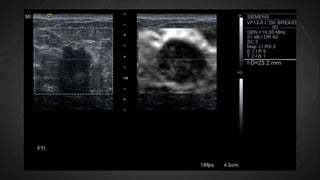

Strain elastography

In this example, the lesion is

compressed much less than the

surrounding tissue, indicating relative

stiffness.

SE is not quantitative and indicates only

the relative hardness or softness of

lesions compared to their surroundings